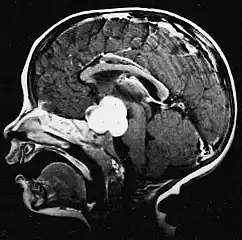

Stereotactic MRI brain scan showing a recurrent postoperative brain stem cystic pilocytic astrocytoma. -

Pilocytic astrocytoma in the hypothalamic region. -

Sagittal T1-weighted MRI showing a well-circumscribed hypointense mass in the tectum (presumably a tectal plate glioma). These lesions are a distinct subset of pilocytic astrocytoma which present with hydrocephalus typically in 6 to 10 year-olds and are rarely progressive lesions. When imaging is characteristic, a biopsy is usually not performed because of the risks to adjacent structures, often shunting to relieve intracranial pressure is the only treatment required. -

T1-weighted coronal MRI image postcontrast showing heterogeneous contrast enhancement within the presumed tectal plate glioma

Usually – depending on the interview of the patient and after a clinical exam which includes a neurological exam and an ophthalmological exam – a CT scan and/or an MRI scan will be performed to confirm the presence of a tumor. They are usually easily distinguishable from normal brain structures using these imaging techniques. A special dye may be injected into a vein before these scans to provide contrast and make tumors easier to identify. Pilocytic astrocytomas are typically clearly visible on such scans, but it is often difficult to say based on imaging alone what type of tumor is present.